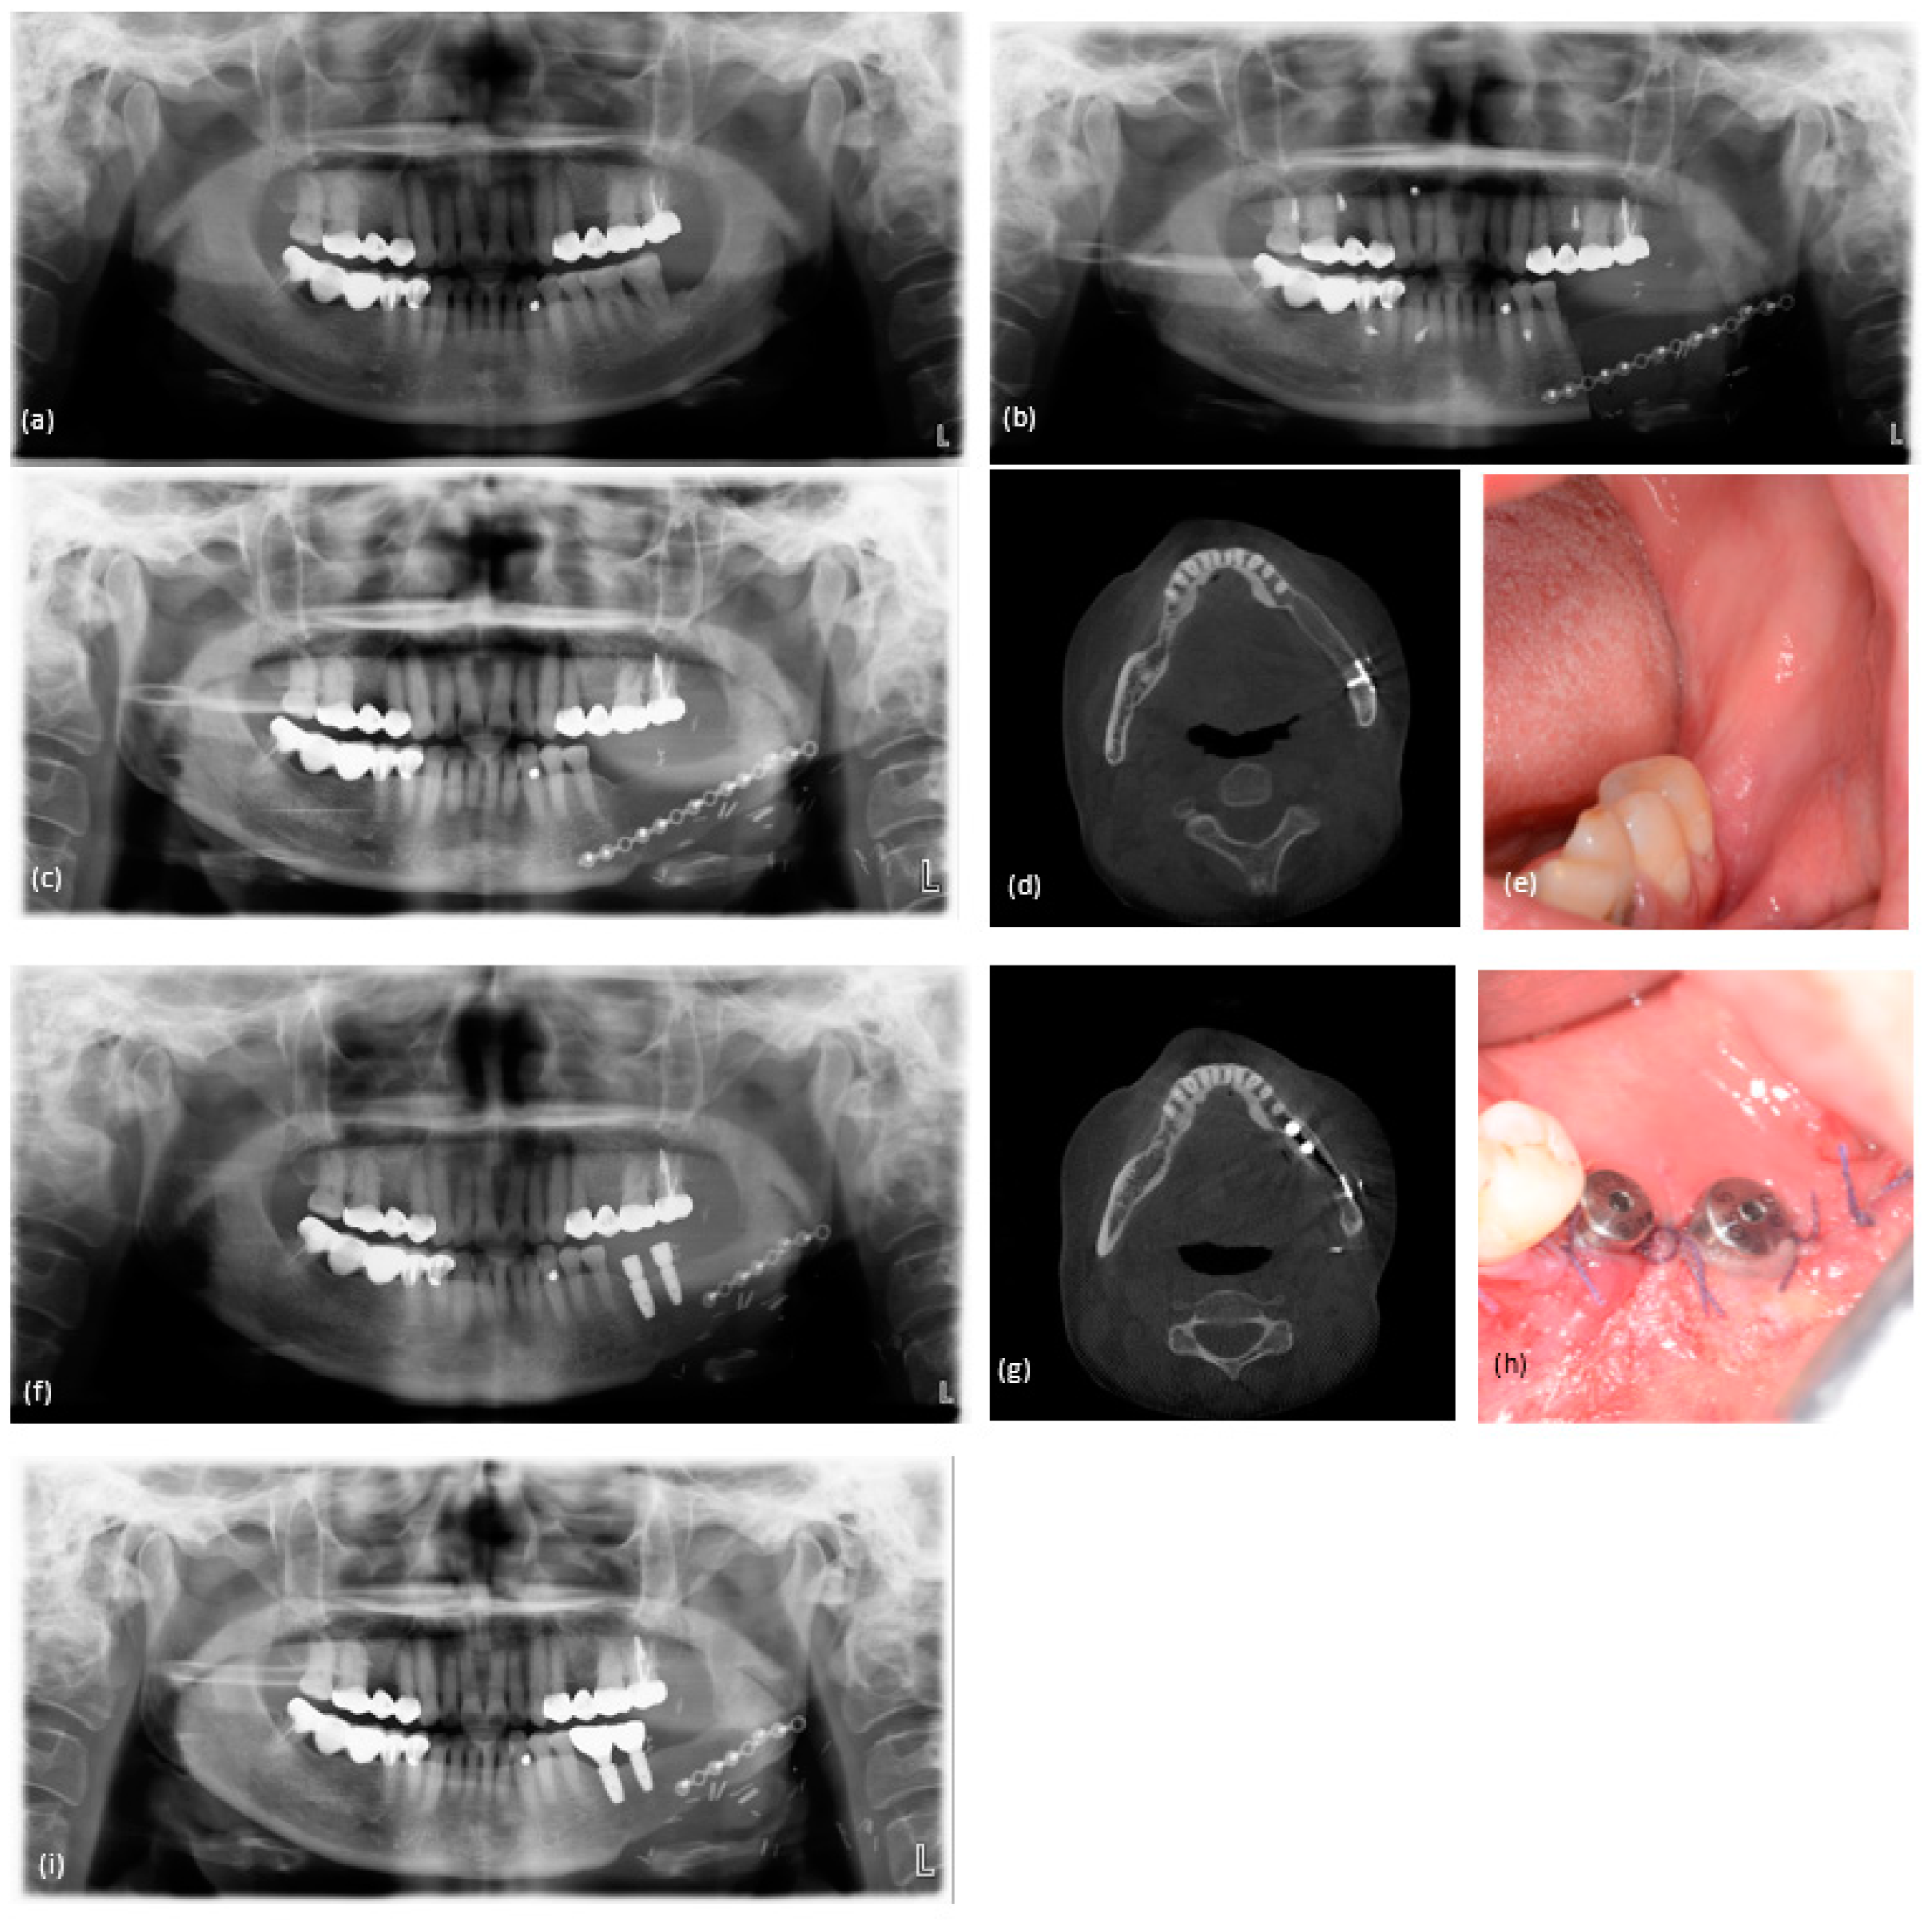

3. Results

3.2. Analysis of Implants

3.3. Evaluation of Peri-Implant Marginal Bone Loss

3.4. Volume of Grafted Bone

3.5. Implant Survival

4. Discussion